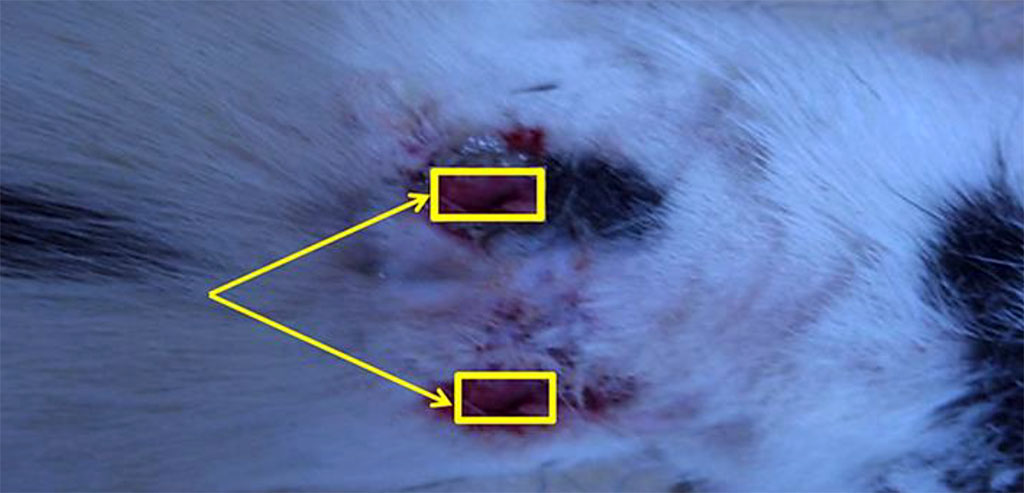

The animals were kept in cages, individually, with free access to food and water. The experiments were carried out in following strictly the European Council Directive on ethical principles in working with laboratory animals (the European Council Directive (86/609/EEC)) and Directive 2010/63/EU of the European Parliament and of the Council of the European Union. There were three experimental groups – 15 animals in each. The models of soft tissue wounds in experimental animals were made with a specially developed technique (Patent RU #2703709 of August 23, 2018). The technique consisted of creating a wound with specified parameters, this done by introducing a hydrophilic polymer implant of spherical shape into soft tissues for 6-7 days. The implant was inserted through a layer-by-layer incision of soft tissues down to the required depth. Further on, the wound was sutured in layers for the above-mentioned period. The implant was removed surgically, and then the tested material was introduced into the cavity. A sterile cloth with Levomekol ointment was applied on top of the studied materials to be further fixed with separate nodular sutures to the wound edges (Figure 1).

Figure 1. Fixation of a sterile napkin with Levomekol ointment to the wound edges of a laboratory animal.